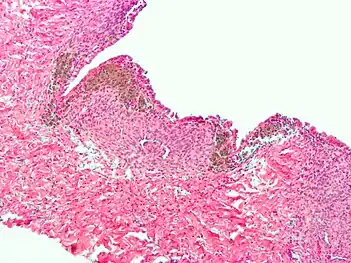

Histopathology

For a histopathological diagnosis, at least two of the following three criteria should be present:[88]

- Endometrial type stroma

- Endometrial epithelium with glands

- Evidence of chronic hemorrhage, mainly hemosiderin deposits

Immunohistochemistry has been found to be useful in diagnosing endometriosis as stromal cells have a peculiar surface antigen, CD10, thus allowing the pathologist go straight to a staining area and hence confirm the presence of stromal cells and sometimes glandular tissue is thus identified that was missed on routine H&E staining.[89]

Endometriosis, abdominal wall

Micrograph showing endometriosis (right) and ovarian stroma (left).

Micrograph of the wall of an endometrioma. All features of endometriosis are present (endometrial glands, endometrial stroma and hemosiderin-laden macrophages).